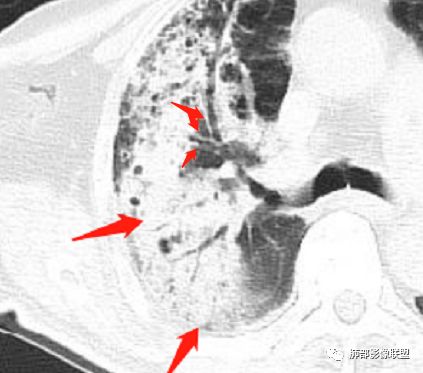

病灶内支气管扩张,迂曲变形,多发空洞,实性成分密度不均,其内可见小斑片状略低密度影,似呈铸形,有增强就更好了。病灶周围边缘相对清晰磨玻璃,有收缩。未见胸腔积液。把肺炎型肺癌放第一位,炎性病变放第二位。

老年男性,咳嗽气喘10天,双肺明显肺气肿,右上肺叶实变,内见大量空洞及囊腔样改变(部分为支气管扩张),实变区周围表现为网格样改变,有明显的小叶间隔增厚,边界似清非清,支气管走行僵硬,有枯树枝样改变,双下肺胸膜下小叶间隔增厚明显,边缘相对模糊,综合考虑如下:1、粘液腺癌可能大(枯树枝样改变,边界似清非清,小叶间隔增厚符合)。2、结核,右上肺似像干酷样改变,内有空洞及支扩样改变支持,但下肺及左肺无相关支气管播散的小叶中心结节及树芽,不支持,临床病症不支持,只有咳嗽,喘气,无咳痰及结核中毒症状。当然结核是妖,需要结合痰检及结核相关指标进一步明确。3、肺克,虽有10年糖尿病史,但肺部只有右肺改变明显,无胸膜下脓肿表现,无脓毒栓表现,临床症状也不支持。4、其他感染?双下肺胸膜下病灶边缘模糊,不完全除外,需要结合临床炎性指标分析。

老年男性,糖尿病患者。右肺病变,病灶区多发树芽、管状透亮区,考虑为扩张支气管,说明为支气管源性病变。结核?真菌?肺癌?病灶区多发空洞,空洞内坏死不太彻底,树芽征跟增殖结节不明显,结核先不考虑。病灶区晕征不太明显,边界相对清楚,小叶间隔增厚~似呈结节状改变,支气管枯树枝征。最后,肺癌首先考虑,粘液腺癌?鉴别曲霉菌

恶性依据主要是有枯树枝样改变,实变周围有网格样增厚的小叶间隔,边界似清非清

2、支气管:干酪样肺炎内的支气管破坏的,扩张的,粘液腺癌小支气管多狭窄的堵塞的,大支气管较完好,枯枝征。